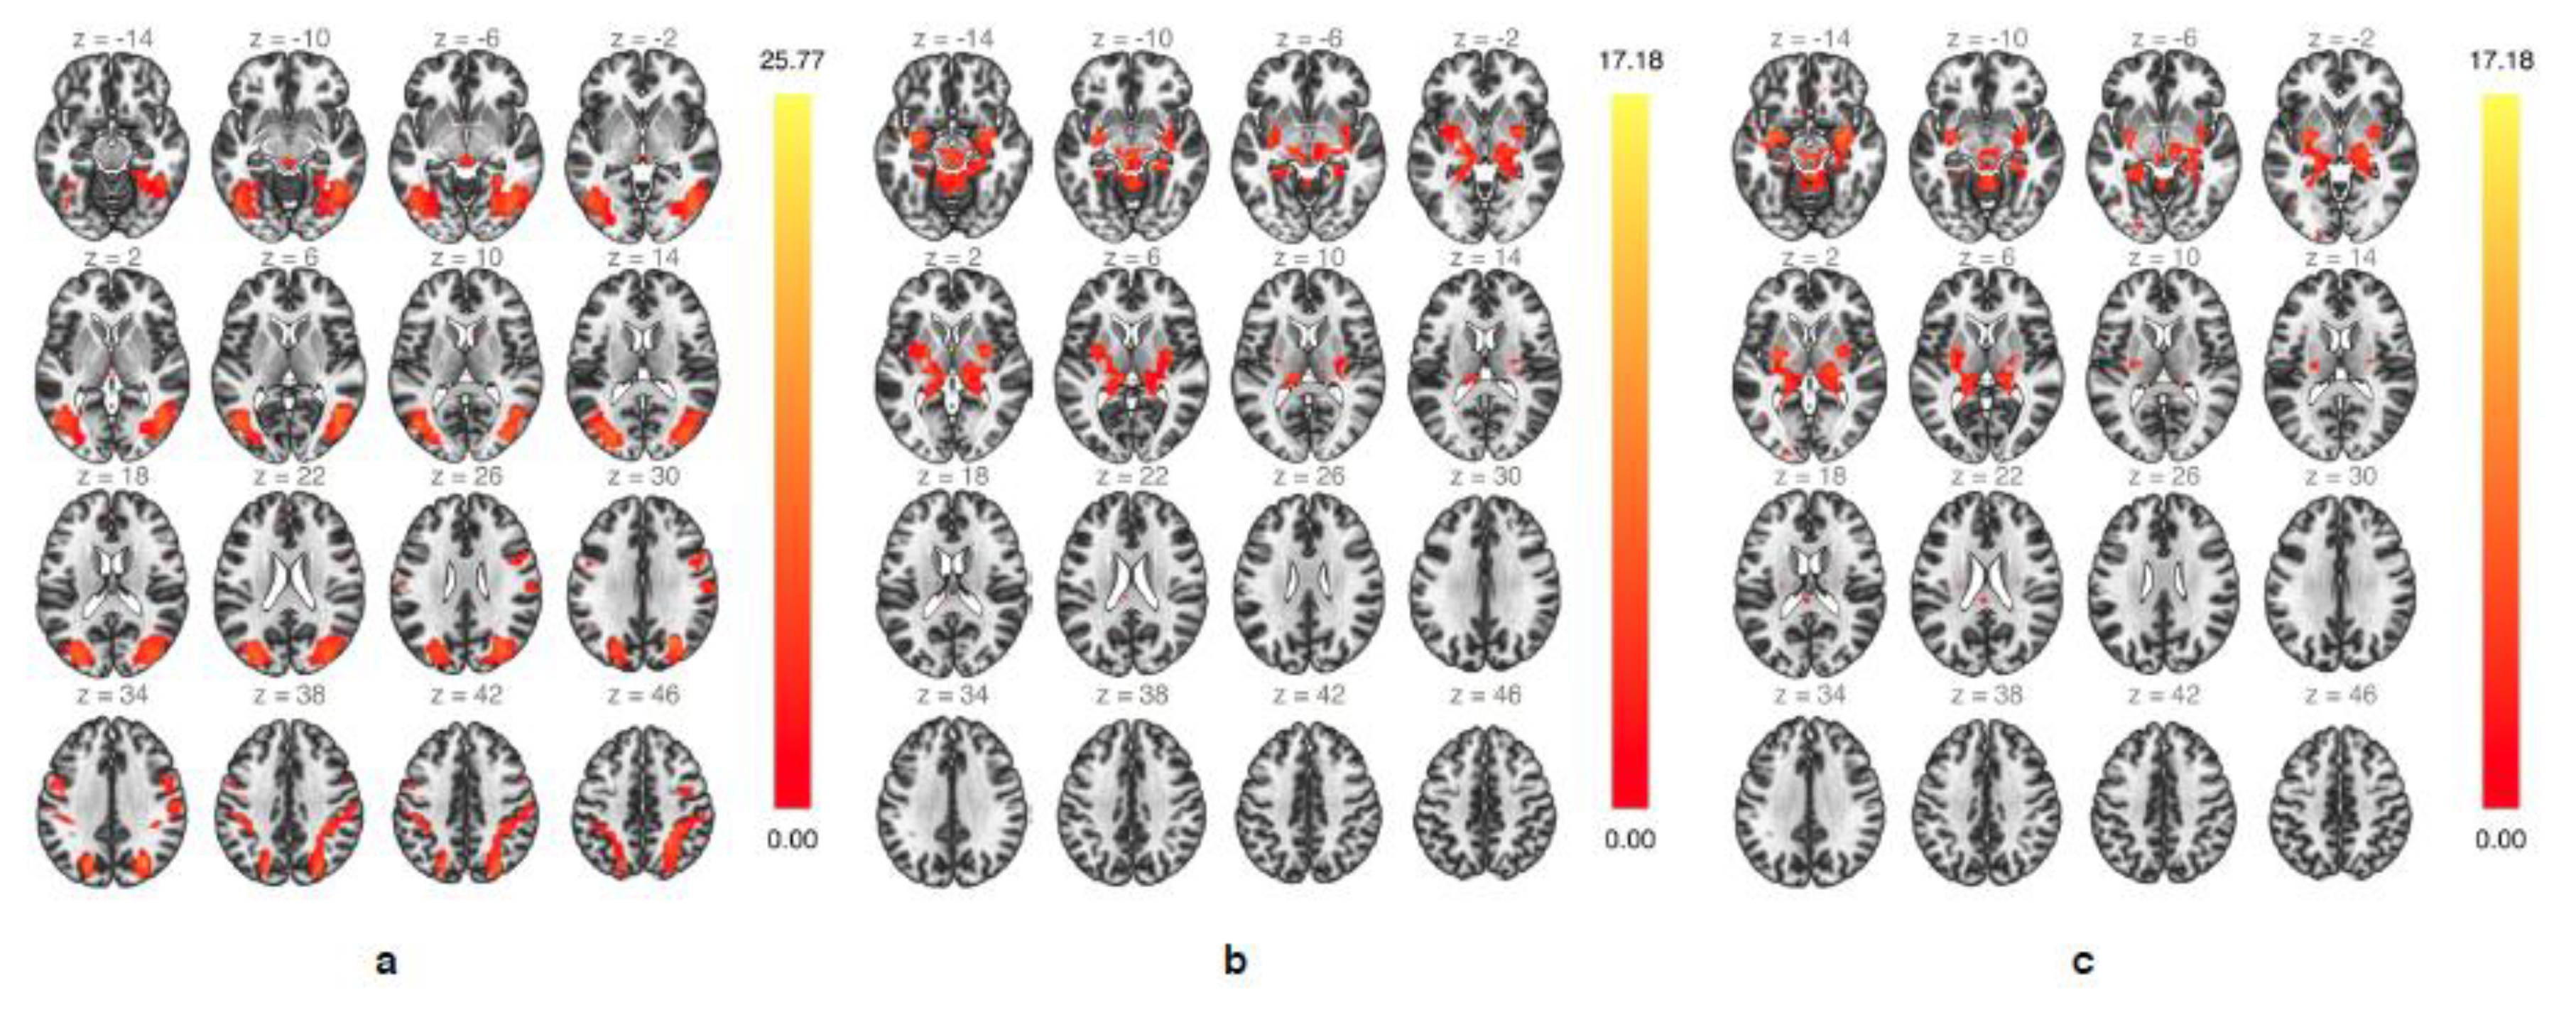

3.2. Whole Brain Group Analysis

| Up > Down | ||||

|---|---|---|---|---|

| K | T | x, y, z (mm) | Hemisphere | Area |

| 200 | 5.88 | −8, 10, 65 | L | SMA |

| 92 | 5.62 | 45, −66, 0 | R | Middle temporal gyrus |

| 81 | 5.28 | −37, 0, 50 | L | Premotor cortex |

| 62 | 5.14 | 5, −26, −10 | R | Midbrain |

| 39 | 5.03 | 18, −10, 25 | R | Caudate nucleus |

| 77 | 4.98 | 42, 0, 50 | R | Premotor cortex |

| 114 | 4.87 | −37, 20, 0 | L | Anterior insula |

| 107 | 4.70 | 42, 13, 5 | R | Anterior insula |

| 47 | 4.19 | 2, −19, 5 | R | Thalamus |